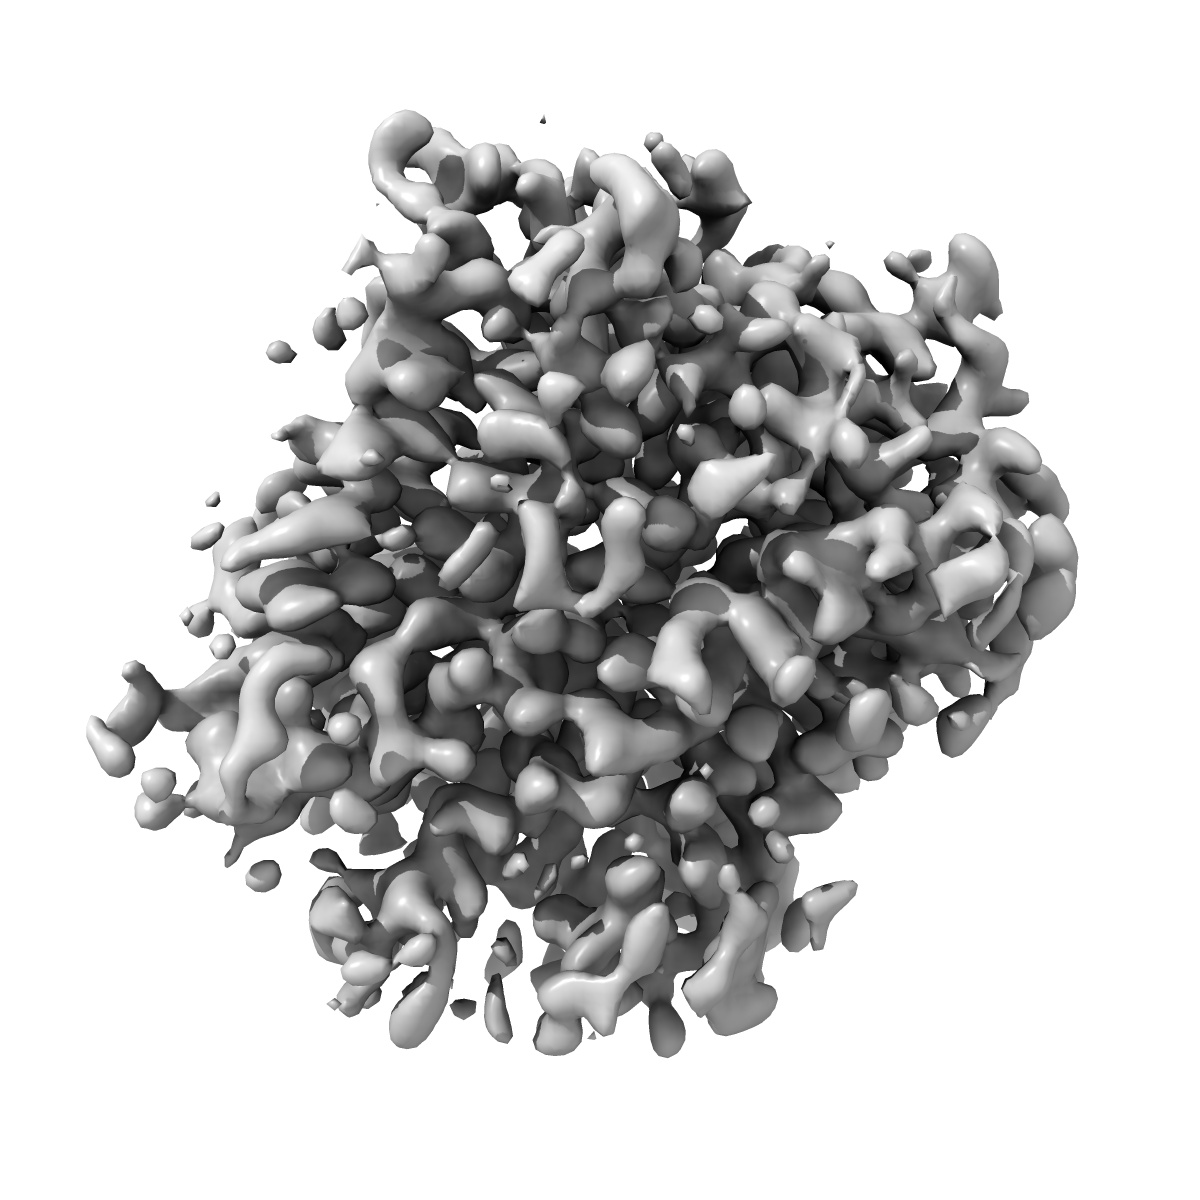

Structure of the human vesicular monoamine transporter 2 (VMAT2) bound to Tetrabenazine in an occluded conformation

Sample: Human VMAT2 complexed with Tetrabenazine

Structural mechanisms for VMAT2 inhibition by tetrabenazine.

Dalton MP , Cheng MH , Bahar I, Coleman JA

(2024) eLife , 12